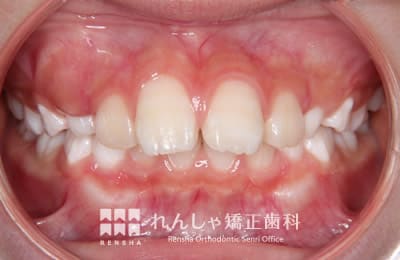

中高生

永久歯列はほぼ完成してしますが、歯列を側方だけでなく後方へも拡大し、埋まっていた右上奥歯を引っ張り出しています。

| 主訴 | 埋まったままでてこない歯がある |

|---|---|

| 診断名 | Angle Class II 小臼歯の埋伏と叢生を伴う上顎前突 |

| 初診時年齢 | 13歳5か月 |

| 装置名 | マルチブラケット装置 |

| 抜歯非抜歯 | 非抜歯 |

| 治療期間 | 2年3か月 |

| 費用の目安 | 約82万円+消費税(検査料金、都度の処置費用等も合わせた総額) |

| リスク副作用 | 歯の移動に伴う軽微な歯根吸収、歯槽骨吸収、歯肉退縮(本症例では軽度の歯根吸収を認めた)、矯正器具装着中のカリエスリスク増大(本症例ではカリエス発生無し) |